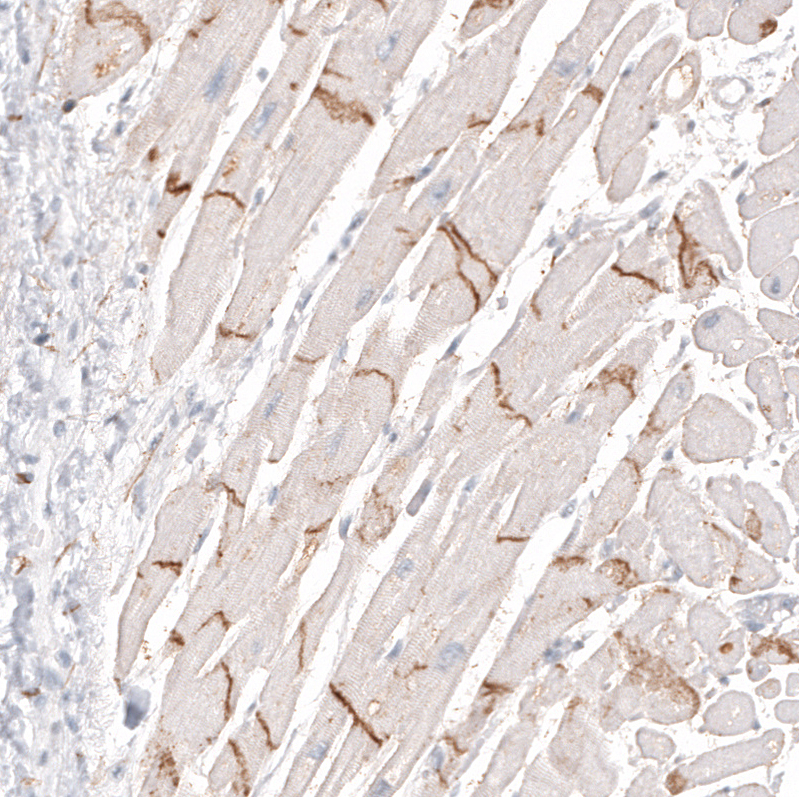

Immunohistochemistry analysis in human cerebral cortex and skeletal muscle tissues using AMAb91807 antibody. Corresponding NCAM1 RNA-seq data are presented for the same tissues.